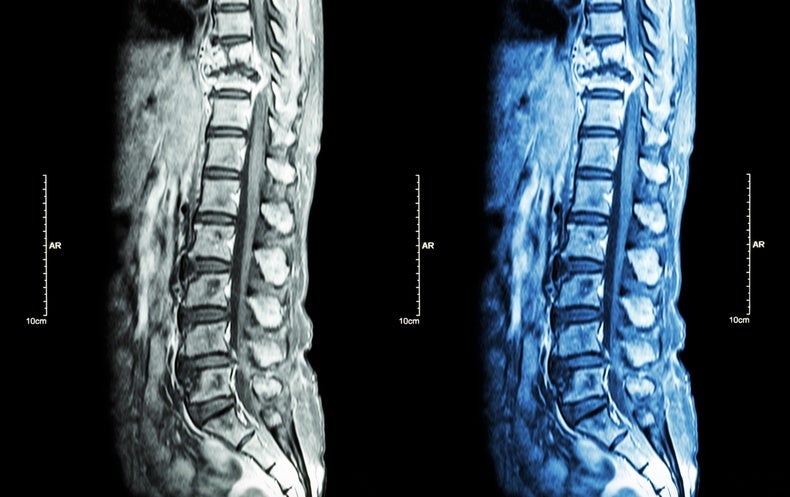

Las espinas son exclusivas de los animales vertebrados, y las vértebras espinales no contienen algunas de las proteínas que a menudo se consideran características de los huesos. Estas características llevaron a Greenblatt y sus colegas a sospechar que se forman mediante un mecanismo diferente al de otros huesos.

Trabajando en ratones, los científicos del laboratorio de Greenblatt aislaron células madre tanto de las vértebras como de los llamados huesos largos, como el fémur de la pierna. Descubrieron que las células madre de los dos lugares expresaban conjuntos de genes marcadamente diferentes. Los científicos insertaron las células vertebrales en los músculos de los ratones y observaron que las células producían una progenie que recordaba la gama de células que se encuentran en la columna vertebral. Esta y otras pruebas los llevaron a concluir que habían descubierto células madre esqueléticas vertebrales o vSSC.